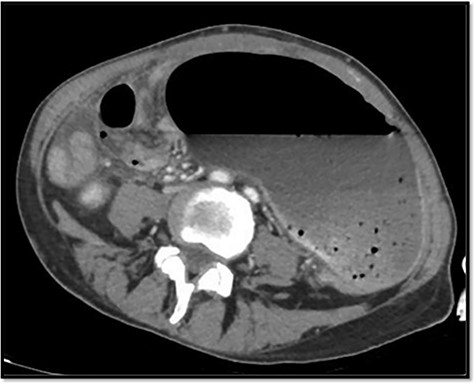

The emergency blood test showed a normochromic and normocytic anemia with an hemoglobin of 10.1 mg/dl and a leukocytosis of 11.150/ul with 70% neutrophils. The abdominal radiography showed a prominent dilation of a small bowel loop. The CT scan reported an 18-cm dilated loop. The main diagnostic suspicion was a small bowel volvulus without signs of ischemia or perforation (Figs 1–3).

With this diagnosis, an emergency laparotomy is performed. It showed a cecum volvulus that compromised 6 cm of distal ileum. The cecum was ischemic, with transmural necrosis. Ileocechectomy was performed including a 15-cm segment of distal ileum. Intestinal transit was reconstructed with mechanical latero-lateral ileo-colic anastomosis with manual reinforcement. The closure of the abdominal wall was performed with a supraaponeurotic prophylactic mesh.